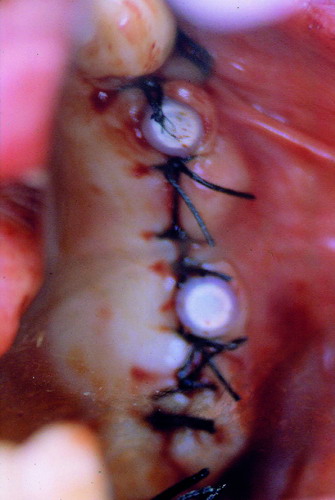

LA OCLUSIÓN MUTUAMENTE PROTEGIDA ES UN VIEJO CONCEPTO QUE CONSISTE EN LA MUTUA INTERACCIÓN DE LOS DISTINTOS GRUPOS DENTARIOS ENTRE SI. DE ESTA FORMA, LA TABLA PREMOLAR / MOLAR DE AMBOS HEMIMAXILARES ANTAGONISTAS, DETIENEN EL CIERRE MANDIBULAR EN CÉNTRICA, LOS CANINOS DISCLUYEN LAS PIEZAS POSTERIORES DURANTE LAS TRANSTRUSIONES, Y EL GRUPO INCISIVO LO MISMO DURANTE LAS PROPULSIVAS. SIN EMBARGO, DICHO CONCEPTO ES LIMITADO A LAS PIEZAS DENTARIAS, SIN TENER EN CONSIDERACIÓN LA IMPORTANTE FUNCIÓN QUE RECAE SOBRE LA ATM Y EN EL SOPORTE DE PRESIONES DURANTE ESTA DINÁMICA. ES ASI QUE EN EL AÑO 1981, EL DR. ANIBAL ALONSO GENERA EN LA CIUDAD DE BUENOS AIRES UN CONCEPTO MAS AMPLIO QUE DENOMINÓ : OCLUSION MUTUAMENTE COMPARTIDA. REF I EN EL QUE AMPLÍA EL CONCEPTO ANTERIOR, HACIENDO PARTÍCIPE A LA ATM EN LA MISMA. CUANDO EXISTE CARENCIA DE PIEZAS DENTARIAS POSTERIORES, YA SEA DE UN SOLO LADO O DE AMBOS , EL CIERRE MANDIBULAR ES DETENIDO POR LAS PIEZAS RESTANTE, FORZANDO A LA ATM A SOPORTAR PRESIONES MUY SUPERIORES A AQUELLAS PARA LAS QUE ESTA PREPARADA. FIG1 FIG2 FIG3 LUEGO DEL ESTUDIO CLÍNICO DE RIGOR, DONDE SE EVALÚA RADIOGRÁFICA Y PERIODONTALMENTE, SE PROCEDE A TOMAR MODELOS DE ESTUDIO Y MONTAR EN ARTICULADOR SEMIAJUSTABLE, SOBRE EL CUAL SE REALIZA UN ENCERADO PROGRESIVO DE DIAGNÓSTICO, A PARTIR DEL CUAL SE CONFECCIONA UN JUEGO COMPLETO DE PROVISIONALES DE AMBAS ARCADAS , INCLUYENDO LAS PIEZAS FALTANTES. SE ABORDA EL CASO YA QUIRÚRGICAMENTE DONDE EN UNA PRIMERA ETAPA SE TALLAN PRIMARIAMENTE LAS PIEZAS DENTARIAS Y SE PROCEDE, EXODONCIANDO EL INCISIVO CENTRAL SUPERIOR DERECHO, A REALIZAR UNA ROG(REGENERACIÓN ÓSEA GUIADA), PARA INMEDIATAMENTE INSTALAR PARTE DE NUESTROS PROVISORIOS EN LA GUIA ANTERIOR. SE ADAPTAN A LOS SECTORES POSTERIORES LAS PRÓTESIS REMOVIBLES QUE PORTABA, Y SE ESPERAN CUATRO MESES, AL CABO DE LOS CUALES SE REALIZA UN ESTUDIO CON DENTASCAN, MEDIANTE EL USO DE UNA FÉRULA RADIOLÓGICA CON TUBOS METÁLICOS , QUE NOS SERVIRÁ TAMBIÉN DE GUÍA QUIRÚRGICA. PROCEDEMOS ENTONCES A LA IMPLANTACIÓN DE LOS SECTORES EDÉNTULOS MEDIANTE IMPLANTES ROSCADOS Y TÉCNICA SEMI SUMERGIDA. TRANSCURRIDAS OCHO SEMANAS OBSERVAMOS UNA CORRECTA SALUD PERIMPLANTARIA, Y REALIZAMOS LA INSTALACIÓN DE LOS ABUTTMENTS ALCANZAMOS ENTONCES EL PUNTO EXACTO DONDE DEBEREMOS COMENZAR A RECONTRUIR EN FORMA PERMANENTE. PAZ DEL SISTEMA: CENTRICIDADARTICULAR-PAZ MUSCULAR-ESTABILIDAD- -ACOPLAMIENTO. BASES FUNDAMENTALES DE LA OCLUSIÓN ORGÁNICA FIG41 FIG42 PROCEDEMOS NUEVAMENTE A TOMAR IMPRESIONES, EN ESTE CASO DEFINITIVAS , MONTAR NUEVAMENTE EN ARTICULADOR, Y CONSTRUIR LAS RESTAURACIONES PERIFÉRICAS TOTALES EN BASE A PORCELANA SOBRE ORO GALVANIZADO. REF. II SOBRE LAS MISMAS TERMINADAS Y YA EN BOCA, CHEQUEÁMOS TODOS LOS ELEMENTOS QUE CONSTITUYEN UNA REHABILITACIÓN ORAL INTEGRAL, DESDE LA SALUD ENDODONTICA DE PIEZAS TRATADAS O NO, LA SALUD PERIODONTAL, EL AJUSTE PERIFÉRICO DE LAS RESTAURACIONES, LA ESTABILIDAD EN LA ATM, Y LAS FUNCIONES OCLUSALES, CHEQUEOS ESTOS QUE SE REPETIRAN EN CADA UNO DE LOS CONTROLES POST OPERATORIOS. FIG46 FIG47 FIG48 FIG66 FIG67 REFERENCIAS: REF I: OCLUSIÓN Y DIAGNÓSTICO EN REHABILITACIÓN ORAL REF. II ELECTROFORMACIÓN EN ODONTOLOGÍA RESTAURADORA.